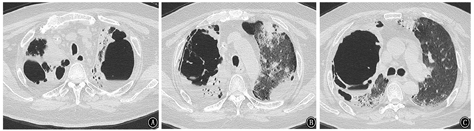

患者男,64岁,因"反复咳嗽、咳痰、喘憋18年,加重20余天"于2018年1月26日入院。患者近18年反复出现咳嗽、咳痰、喘憋,诊断为COPD、肺气肿、肺大疱、矽肺Ⅰ期等。近3年因COPD急性加重多次住院,经抗感染、化痰、平喘等治疗可好转,院外长期吸入沙美特罗替卡松粉(舒利迭)、噻托溴铵粉(思力华),口服止咳、化痰药物。2018年1月3日患者受凉后再次出现咳嗽、咳痰、喘憋加重,就诊于北京某医院。2018年1月3日胸部CT示两肺见多发粗大索条影,边缘模糊,肺气肿,多发肺大疱,左肺下叶球形肺不张,双侧胸膜肥厚,右侧胸膜钙化,右肺下叶支气管扩张(图1),考虑肺部感染。住院后给予哌拉西林舒巴坦钠、比阿培南、莫西沙星等抗感染,并给予甲泼尼龙抗炎(具体不详)。患者病情好转,于2018年1月24日出院。出院后按医嘱继续口服醋酸泼尼松40 mg/d。2018年1月26日患者出现发热,体温最高达38 ℃,咳嗽、咳痰、憋喘较前加重,安静状态憋喘,咳痰带鲜红血丝,伴纳差、乏力,无盗汗,无胸痛,无头晕、恶心,来北京老年医院急诊就诊。血常规:白细胞计数23.69×109/L,红细胞计数5.42×1012/L,血红蛋白158 g/L,血小板计数173×109/L,中性粒细胞比例87.3%,淋巴细胞比例5.7%;血气分析:pH值7.45,PaCO2为41.4 mmHg(1 mmHg=0.133 kPa),PaO2为72.2 mmHg,SaO2为94.5%;血凝指标、D-二聚体、肌钙蛋白I、肌酸激酶同功酶、B型钠酸肽均正常。2018年1月26日胸部CT与2018年1月3日比较,双肺新出现散在斑片影及斑点影,伴大小不等空洞,部分空洞周围可见晕征(图2),考虑双肺感染进展,收住北京老年医院呼吸康复科。